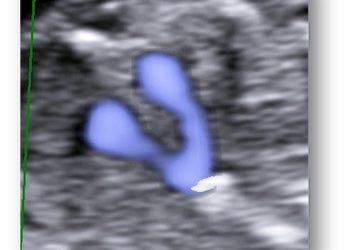

Casi del Mese di Marzo 2021

Cari soci, ecco la soluzione dei casi del mese di marzo! Caso Ostetrico ...